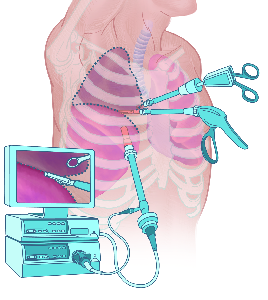

Detailreiche Fotografien aus der medizinischen Praxis ergänzen die Texte; moderne, genaue,

wissenschaftliche Zeichnungen geben Einblick in die Anatomie und die Funktion der Lunge und

anderer Organe.